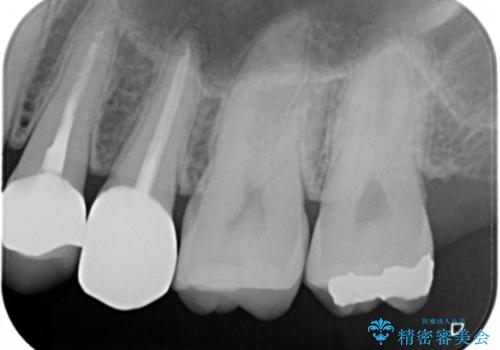

- 左上7番の銀歯のやり変えを希望された患者様です。

セラミックでの治療を希望されたため切削量などを考慮し、セラミックインレーでの治療を計画しました。

銀歯を除去し形態を整えたのち、印象しています。